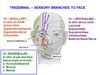

Nerve - CN5iii (mandibular branch of Trigeminal), Chorda tympani (CN7), Otic ganglion (parasympathetic nerve)

Contents are CNVii (Maxillary)